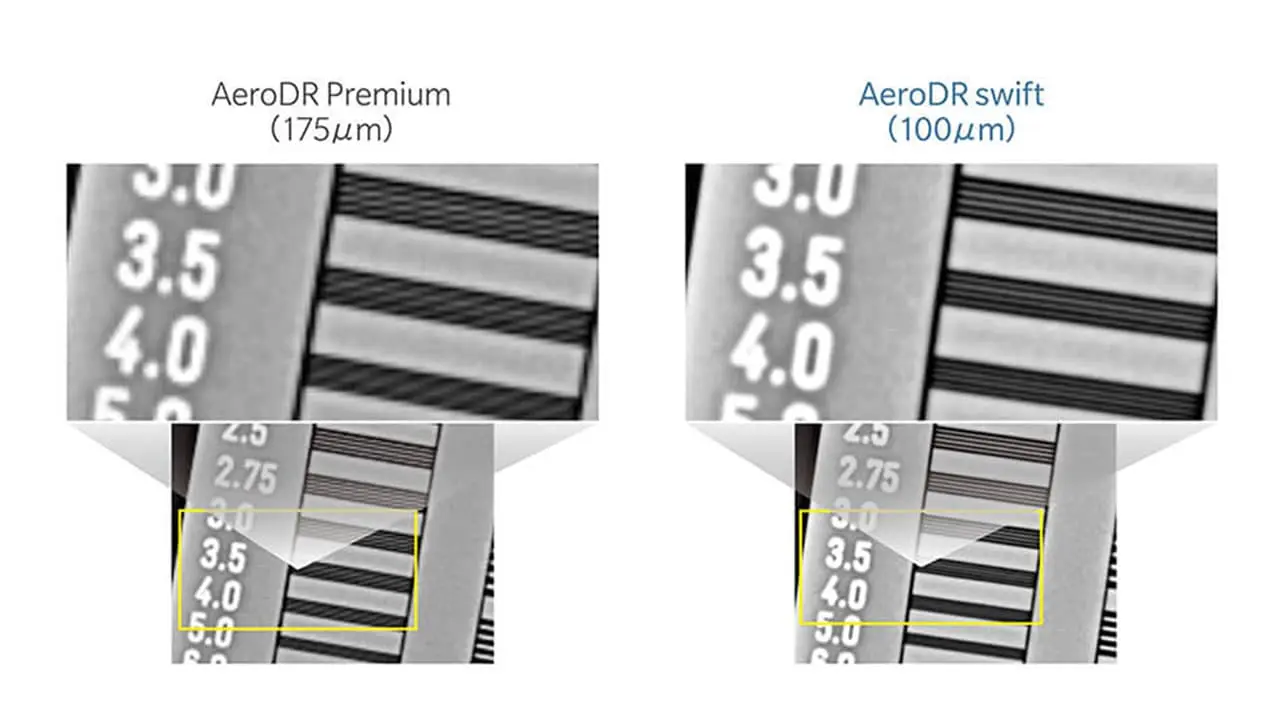

高解像度 100/200μm画素サイズ

AeroDR swiftは画素サイズ100μmを実現。100μm/200μmを撮影部位に応じて使い分ける事ができます。